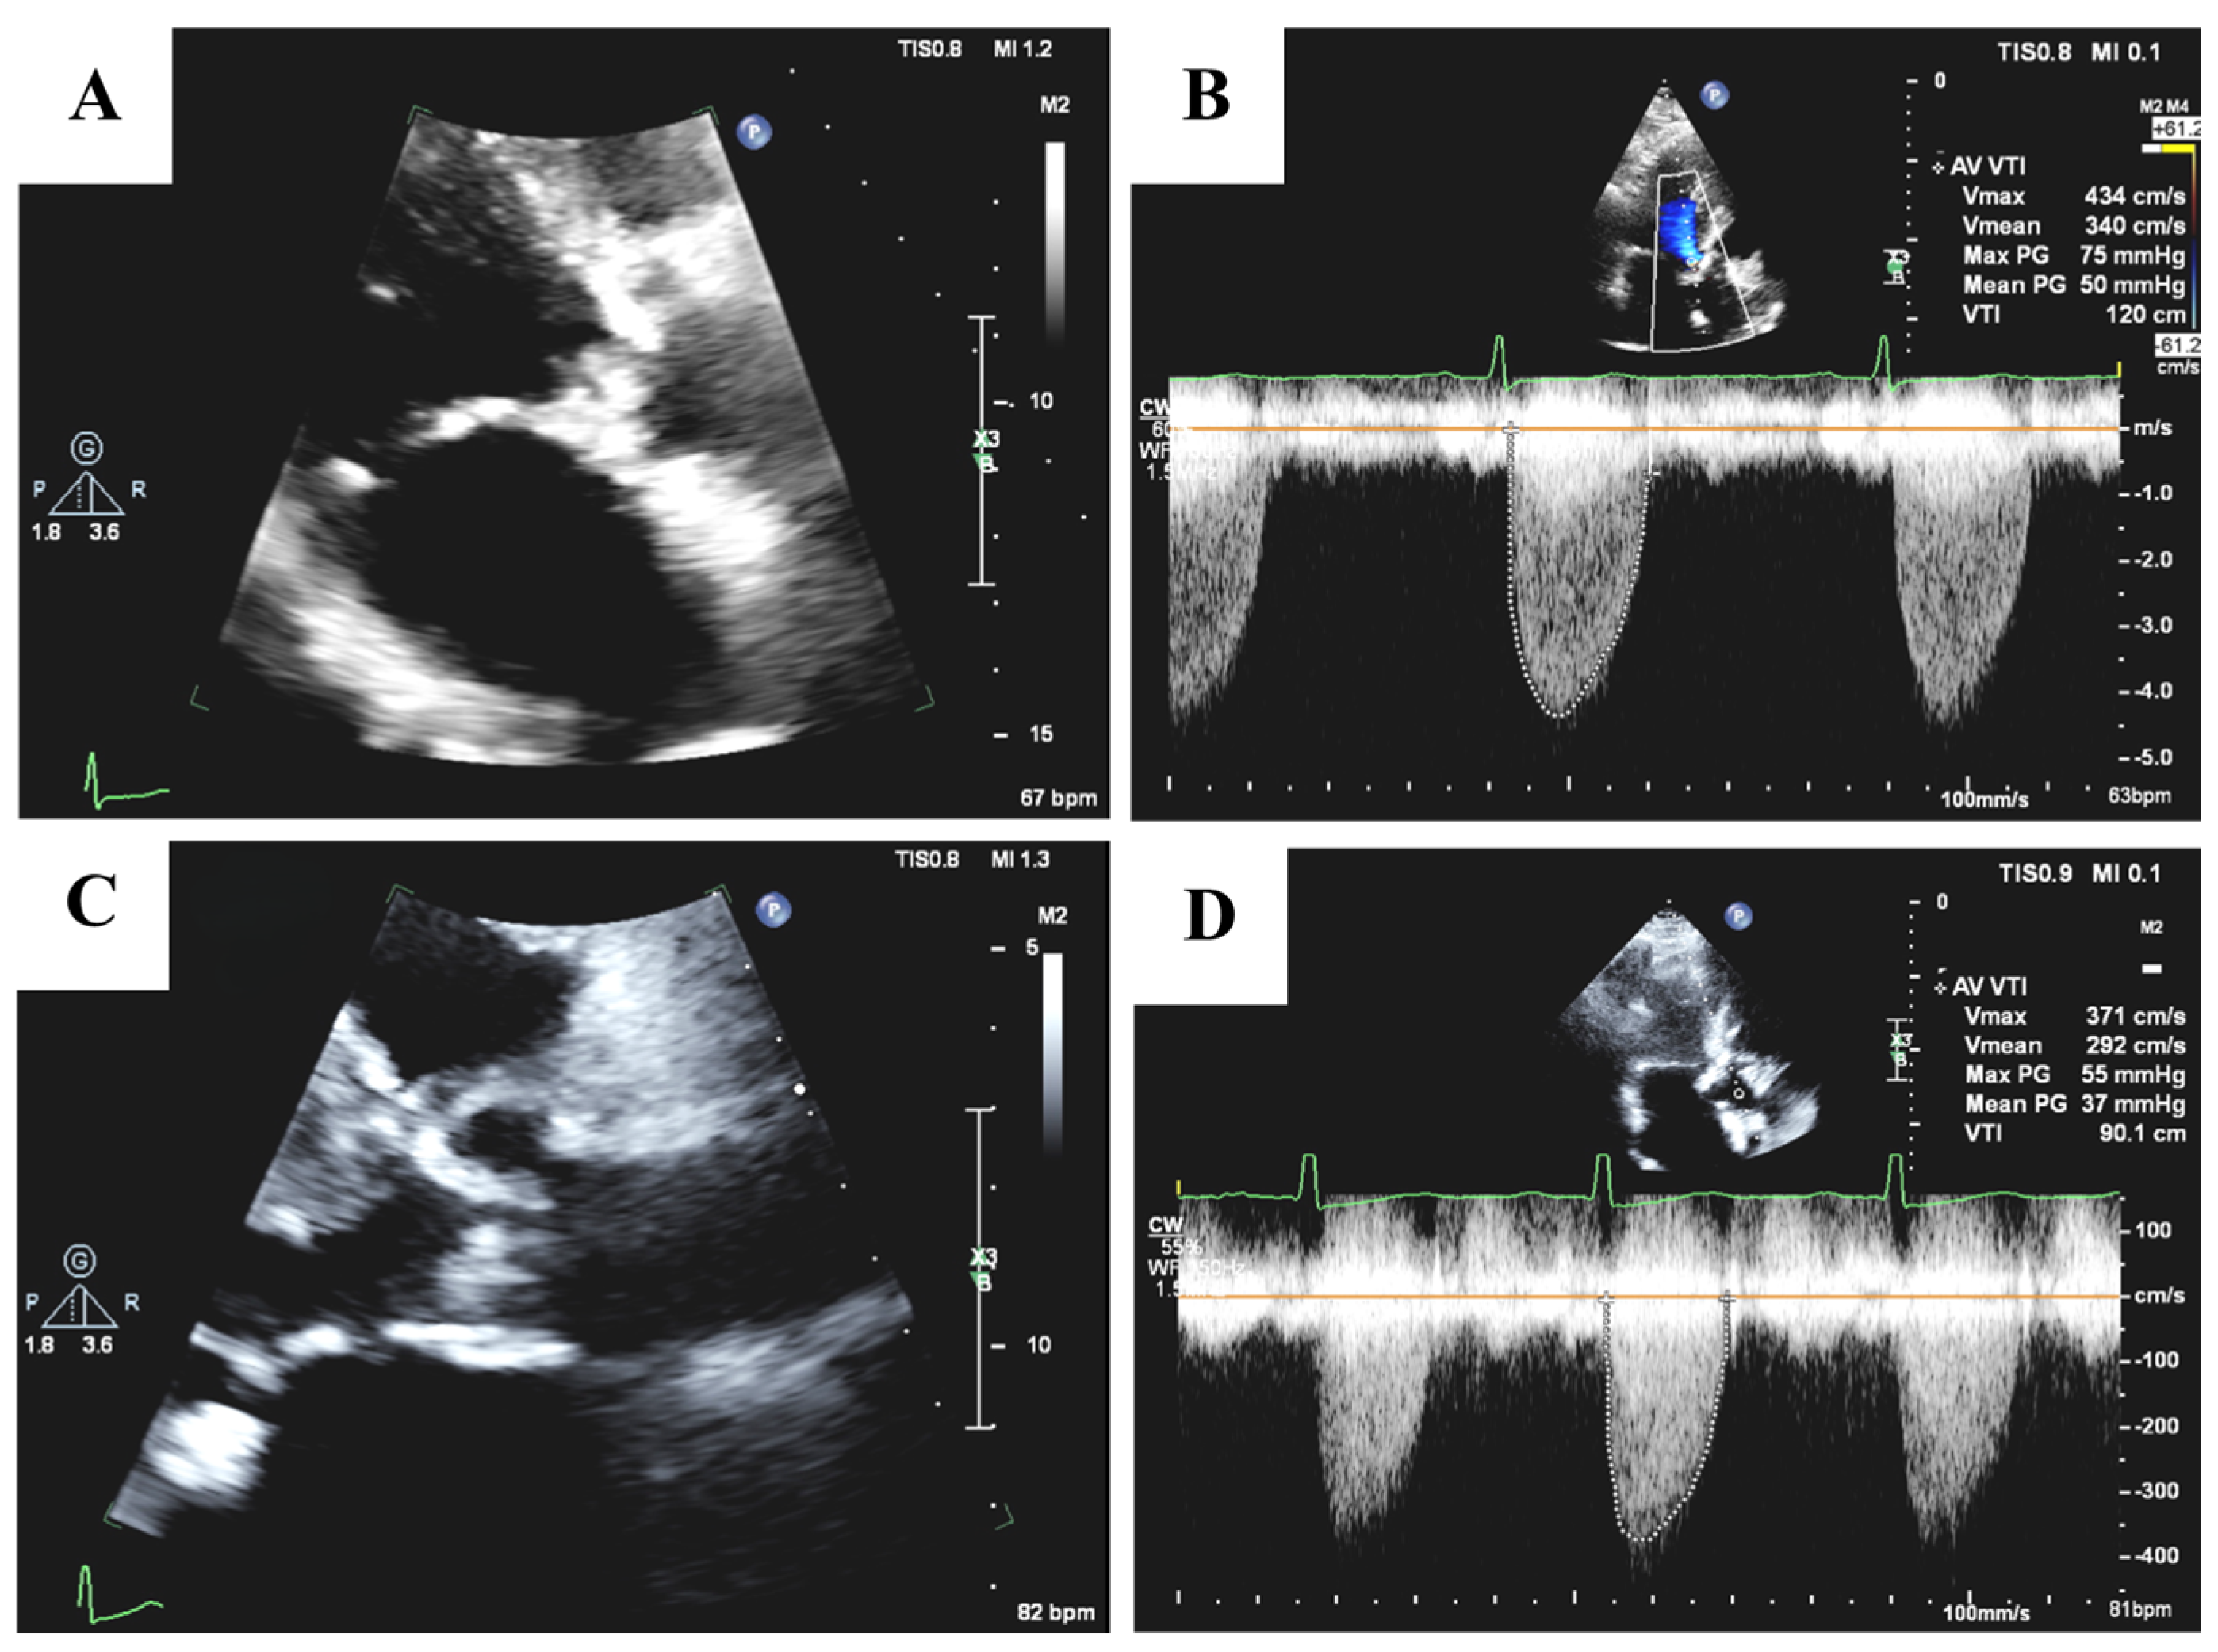

3.1. Echocardiography

- Baumgartner, H.; Hung, J.; Bermejo, J.; Chambers, J.B.; Edvardsen, T.; Goldstein, S.; Lancellotti, P.; LeFevre, M.; Miller, F., Jr.; Otto, C.M. Recommendations on the echocardiographic assessment of aortic valve stenosis: A focused update from the European Association of Cardiovascular Imaging and the American Society of Echocardiography. Eur. Heart J. Cardiovasc. Imaging 2016, 18, 254–275. [Google Scholar] [CrossRef]